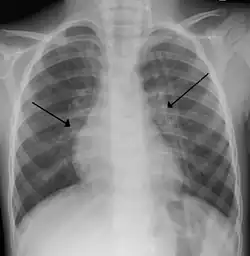

Imaging findings

Chest X-ray findings in children with RSV bronchiolitis are generally nonspecific and include perihilar markings, patchy hyperinflation, and atelectasis.[20] However, the American Academy of Pediatrics (AAP) does not recommend routine imaging for children with presumed RSV bronchiolitis because it does not change clinical outcomes and is associated with increased antibiotic use.[20][5] Chest X-ray is sometimes considered when the diagnosis of bronchiolitis is unclear or when there is an unexpected worsening.[5] In adults with RSV infection, chest films are often normal or demonstrate nonspecific changes consistent with viral pneumonia, such as patchy bilateral infiltrates.[45]